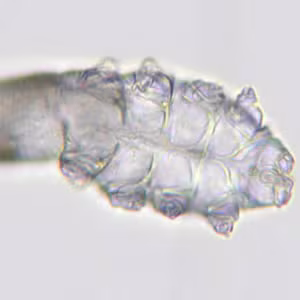

Sarcoptes scabiei mites.

. This form molts into slightly larger nymphs before molting into adults. Larvae and nymphs may often be found in molting pouches or in hair follicles and look similar to adults, only smaller. Adults are round, sac-like eyeless mites. Females are 0.30 to 0.45 mm long and 0.25 to 0.35 mm wide, and males are slightly more than half that size. Mating occurs after the active male penetrates the molting pouch of the adult female

. Mating takes place only once and leaves the female fertile for the rest of her life. Impregnated females leave their molting pouches and wander on the surface of the skin until they find a suitable site for a permanent burrow. While on the skin’s surface, mites hold onto the skin using sucker-like pulvilli attached to the two most anterior pairs of legs. When the impregnated female mite finds a suitable location, it begins to make its characteristic serpentine burrow, laying eggs in the process. After the impregnated female burrows into the skin, she remains there and continues to lengthen her burrow and lay eggs for the rest of her life (1-2 months). Under the most favorable of conditions, about 10% of her eggs eventually give rise to adult mites. Males are rarely seen; they make temporary shallow pits in the skin to feed until they locate a female’s burrow and mate.